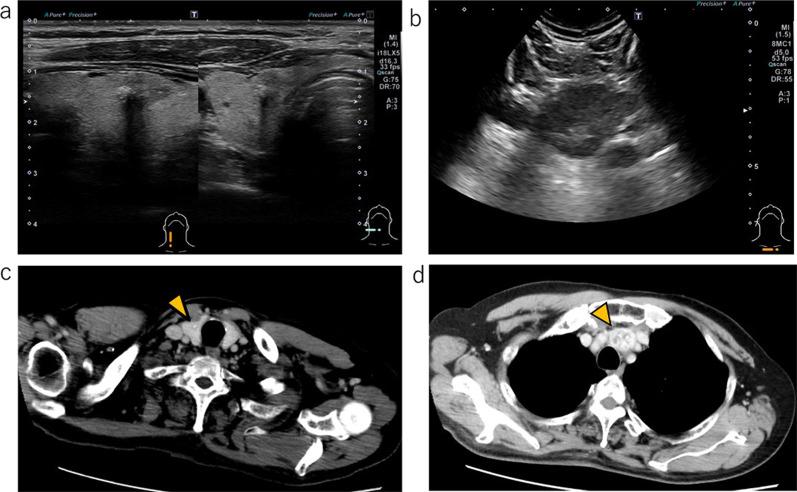

We report a case of MMFCC treated with selpercatinib. The patient was a 69-year-old male presenting with tumors in the right thyroid lobe and in the upper mediastinum. Fine-needle aspiration (FNA) cytology of the right thyroid lobe tumor revealed a medullary carcinoma; germline RET mutations were not detected. After resection of the right thyroid lobe with central node dissection, rapid intraoperative diagnosis of the mediastinal mass confirmed malignancy, leading to total thyroidectomy with excision of the upper mediastinal tumor. Histologically, the tumor in the right thyroid lobe and the pretracheal lymph node revealed a mixture of medullary and follicular carcinoma components, diagnosed as MMFCC. The mediastinal lymph node exhibited only medullary carcinoma components. At 11 months postoperatively, computed tomography scans showed enlargement of the right supraclavicular and upper mediastinal lymph nodes. FNA cytology of the right supraclavicular lymph node suggested the recurrence of medullary thyroid carcinoma. The gene panel testing (The Oncomine Dx Target Test Multi-CDx system®, Thermo Fisher SCIENTIFIC) of metastatic lymph node revealed RET somatic mutation (M918T). Treatment with selpercatinib was initiated, and both the cervical and mediastinal lymph nodes showed a reduction in size.

我们报告1例接受塞尔帕替尼治疗的MMFCC患者。该患者为69岁男性,表现为右甲状腺叶及上纵隔肿瘤。右甲状腺叶肿瘤的细针穿刺(FNA)细胞学检查显示为髓样癌;未检测到胚系RET突变。在切除右甲状腺叶并进行中央淋巴结清扫后,术中对纵隔肿块的快速诊断证实为恶性,遂行全甲状腺切除术并切除上纵隔肿瘤。组织学检查显示,右甲状腺叶和气管前淋巴结的肿瘤呈现髓样癌和滤泡癌成分的混合,诊断为MMFCC。纵隔淋巴结仅表现为髓样癌成分。术后11个月,计算机断层扫描显示右锁骨上和上纵隔淋巴结肿大。右锁骨上淋巴结的FNA细胞学检查提示甲状腺髓样癌复发。转移淋巴结的基因检测(Oncomine Dx Target Test Multi-CDx系统,赛默飞世尔科技公司)显示RET体细胞突变(M918T)。开始使用塞尔帕替尼治疗后,颈部和纵隔淋巴结均缩小。